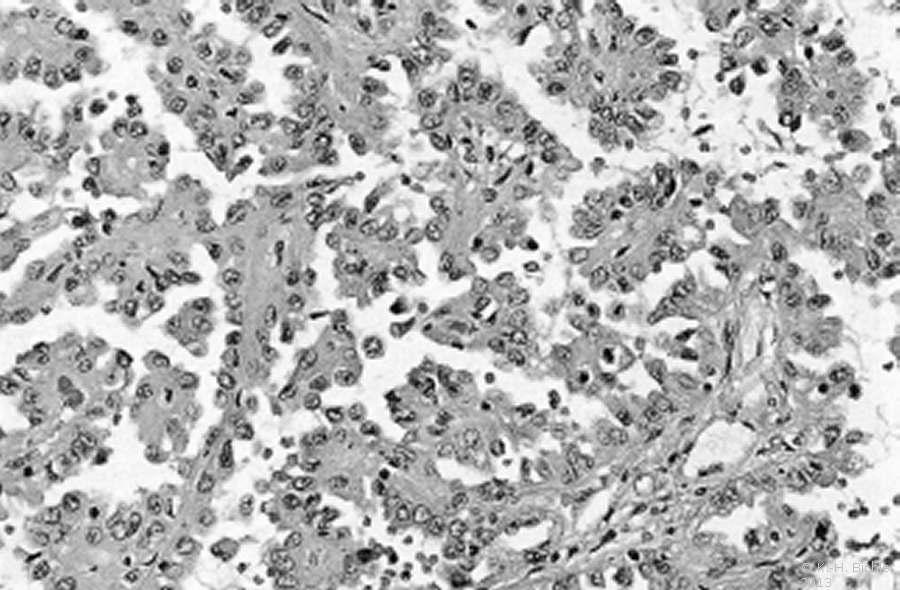

Nierenzellkarzinome im Kindesalter treten als Bestandteil des von Hippel-Lindau-Syndroms, zum Teil auch beidseitig, auf (Abbildung 4)

Literatur:Salome, F. et al: "Renal Lesions in von Hippel-Lindau Disease: The Benign, the Malignent, the Unknown", Eur Urol 34, 383-392, 1998. Das von Hippel-Lindau-Syndrom ist eine autosomal-dominant vererbte Anlagestörung der embryonalen Gefäßorganisation (Angioblastome). Ursache sind Mutationen eines Gens im Chromosom 3. Durch diese Veränderung wird ein Protein nicht mehr gebildet, das eine Schutzfunktion gegenüber Gefäßen, Drüsen und Nierenzellen hat. Knaben sind häufiger betroffen als Mädchen. Die Prävalenz liegt zwischen 1:20.000 und 1:50.000

Literatur:Rahner, N., Steinke, V.: "Erbliche Krebserkrankungen", DÄB, 105, 706-715, 2008. Die Läsionen an der Retina (Angiomatosus retinae- v. Hippel) und das Hämangioblastom des ZNS -im Kleinhirn meist zystisch- Lindau Tumor bezeichnen das Krankheitsbild: von Hippel-Lindau-Syndrom (Abbildung 4)

Beginnend im 3. Embryonalmonat, in dem die Retina vaskularisiert wird, wird die Erkrankung meist erst im 2. Lebensjahrzehnt manifest. Es finden sich polytope angioblastische Fehlbildungen (Retina, ZNS, Nebenniere und Nebenhoden), häufig kombiniert mit viszeralen zystischen und tumorösen Veränderungen (Nierenzellkarzinome, Pankreaskarzinome, Phäochromozytome). Das Nierenzellkarzinom stellt die häufigste Todesursache dar